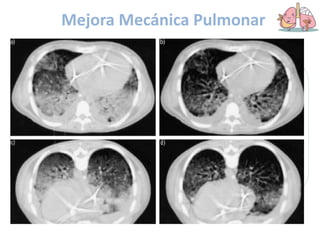

Mejora la mecánica

pulmonar

2

Mejora Mecánica Pulmonar

 Aumento de la rigidez de

la pared torácica

 No se afecta la rigidez

pulmonar o disminuye

 Reclutamiento

Efectos sobre la

PARED TORACICA

 El corazón reposa sobre

la pared torácica, la

compresión disminuye y

el pulmón puede ser

mejor ventilado

Efectos sobre el

CORAZON